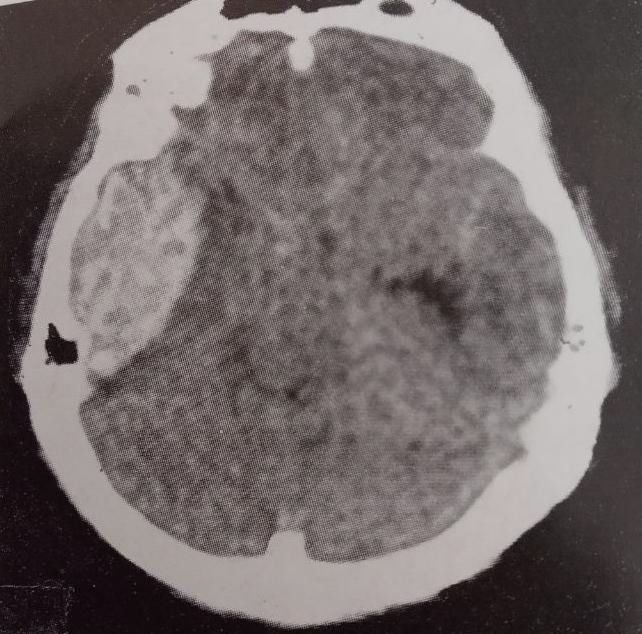

Це крововилив що розташовується між твердою (дуральною) оболонкою мозку і власне мозковою тканиною. На комп’ютерній томографії ці гематоми являти собою зону в формі серпа, часто з поширенням над поверхнею всієї півкулі мозку. Це найчастіший вид гематом що утворюється в порожнині черепа.

Оскільки ця гематома може стискати місцеві структури мозку, це є дуже небезпечним і потребує невідкладної медичної допомоги. Субдуральну гематому можна виявити за допомогою:

- магнітно-резонансної томографії (МРТ)

- або комп’ютерної томографії (КТ) головного мозку.